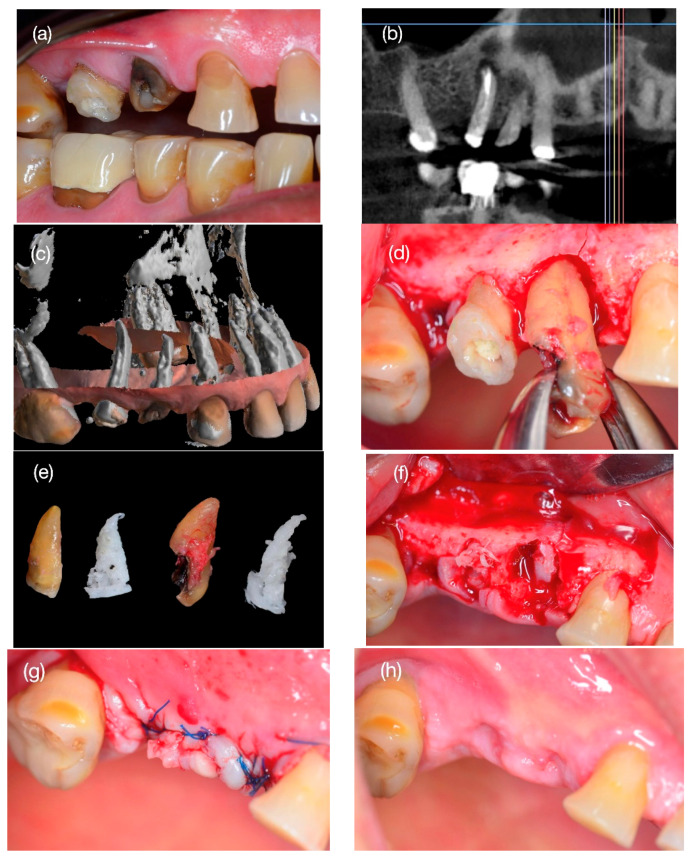

背景与临床意义:通过电喷雾技术对聚己内酯(PCL)三维打印、聚己内酯-嵌段聚乙二醇(PCL- peg)共聚物涂层增强的定制可吸收支架进行放射学和组织学分析,描述其牙槽嵴保存的有效性。病例介绍:一名62岁男性,14号和15号牙齿垂直根骨折。利用锥形束CT (cone beam CT, CBCT)图像,根据支架根的形状设计支架根的复制品,并通过电喷雾的方法将PCL涂覆在PCL- peg上进行打印。将支架插入牙槽骨,并通过无张力皮瓣关闭维持。六个月后,对手术部位进行CBCT检查,并对种植体安装部位的骨样本进行组织学分析。6个月后,14号牙伤口愈合,临床证实无不良反应及并发症。骨样本的组织学分析显示新骨形成具有板层结构、哈弗氏管结构和骨细胞间隙。然而,15号牙的支架是暴露的,没有骨整合,并且被膜组织覆盖。组织学上,样本显示组织与松弛的结缔组织相容,并伴有混合炎症浸润。在第14颗牙齿中,种植体的插入扭矩为bb0 35 Ncm,安装3个月后恢复。结论:三维打印PCL支架具有再生生命骨和功能骨的能力,具有骨整合能力,可用于种植牙的上颌骨再生和口腔康复。一例不充分的支架骨整合伴随着松散的结缔组织形成。

Background and Clinical Significance: To describe the effectiveness of alveolar ridge preservation under the radiological and histological analysis of a customized resorbable scaffold three-dimensionally printed with polycaprolactone (PCL) reinforced with a coating of a copolymer of polycaprolactone-block-polyethylene glycol (PCL-PEG) by electrospray. Case Presentation: A 62-year-old male with vertical root fractures of teeth #14 and #15. From the cone beam CT (CBCT) image, the scaffold root replicas were designed with the shape of the roots and printed with PCL coated with PCL-PEG by electrospray. The scaffold was inserted into the alveolar bone and maintained with a tension-free flap closure. After six months, a CBCT of the surgical site and histological analysis of a bone sample at the dental implant installation site were performed. After 6 months, the wound in tooth #14 was closed, clinically proving no adverse reaction or complications. The histological analysis of the bone sample showed new bone formation with lamellar structure, Haversian canal structure, and osteocyte spaces. However, the scaffold in tooth #15 was exposed and not osseointegrated, and it was covered with membranous tissue. Histologically, the sample showed tissue compatible with lax connective tissue with mixed inflammatory infiltrate. In tooth #14, the dental implant presented an insertion torque >35 Ncm and was rehabilitated three months after its installation. Conclusions: Three-dimensional printed PCL scaffolds showed the ability to regenerate vital and functional bone with osseointegration capability for maxillary bone regeneration and oral rehabilitation based on dental implants. A case of inadequate scaffold osseointegration accompanied by lax connective tissue formation is shown.